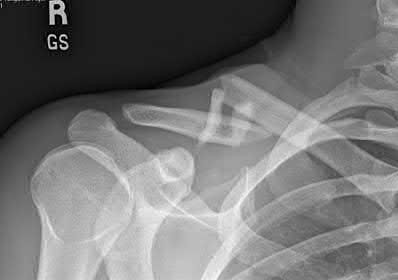

Question 10:

A 30-year-old male presents in hypotensive shock following a motorcycle crash. Pelvic radiographs and CT demonstrate an anteroposterior compression type III (APC-III) injury according to the Young-Burgess classification. Which of the following ligamentous complexes are completely disrupted in this specific injury pattern?

Correct Answer: Symphysis pubis, sacrotuberous, sacrospinous, anterior and posterior sacroiliac ligaments

Explanation:

The Young-Burgess classification for APC injuries relies on progressive disruption of the pelvic ring from anterior to posterior. APC-I involves pubic diastasis <2.5 cm with intact posterior ligaments. APC-II involves diastasis >2.5 cm with disruption of the anterior sacroiliac (SI), sacrotuberous, and sacrospinous ligaments, but intact posterior SI ligaments (rotationally unstable, vertically stable). APC-III involves complete disruption of both the anterior and posterior SI ligaments, resulting in a globally (rotationally and vertically) unstable hemipelvis.